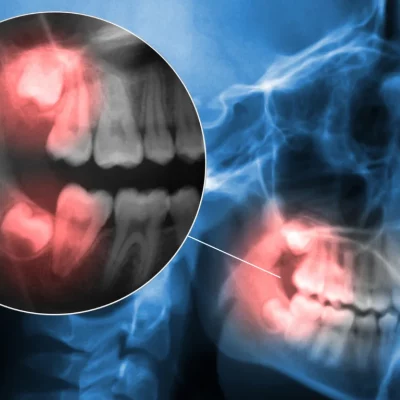

Our experienced team is pleased to provide a full spectrum of general dentistry services, from simple checkups and cleanings all the way through complex treatments such as dental implants, crowns, bridges, root canals and extractions.